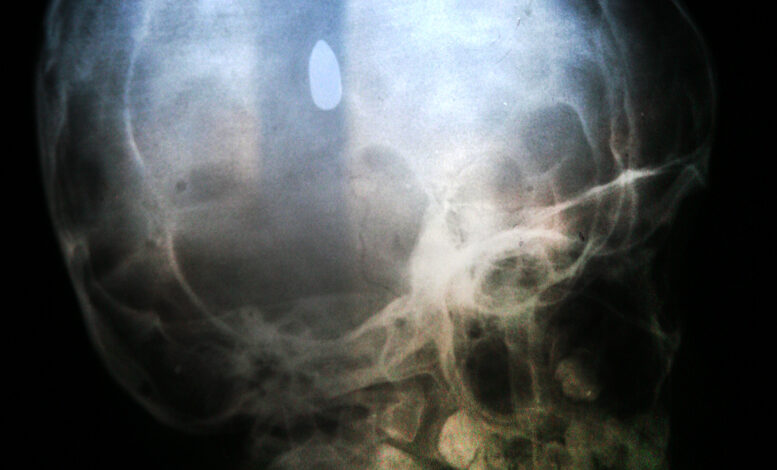

Ο Χαμτίμ ήταν πεσμένος στο χώμα, σταλιά αίμα, πουθενά. Ο Χαμτίμ δεν κινιόταν, ανέπνεε όμως. Το ίδιο βράδυ μας το είπαν οι γιατροί στο νοσοκομείο της Γάζας οπού τον είχαμε μεταφέρει: “Η σφαίρα έχει σφηνώσει στο κεφαλάκι του. Ο στρατιώτης που τον πυροβόλησε πρέπει να ήταν μακριά”.

Τέσσερις μήνες έμεινε σε κώμα ο Χαμτίμ, ώσπου…